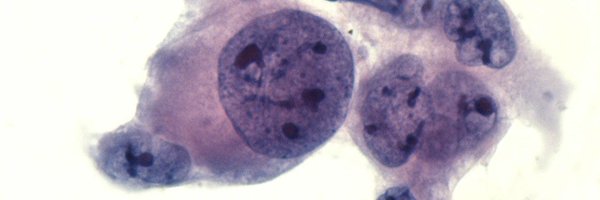

@TotalCytopath

FNA of a cervical lymph node in a woman with a history of breast carcinoma of apocrine type.